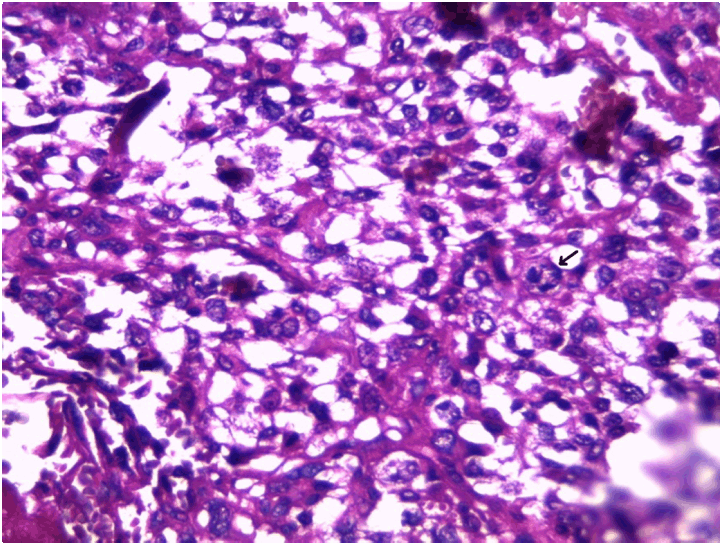

At the pathology laboratory, we received a piece of the left lower limb amputation. (Figure 2) We opened it. Gross examination of the resected distal femur revealed a 22x5 cm intramedullary multicystic hemorrhagic destructive tumor with cortical destruction and extension into the adjacent anterior and posterior soft tissues. The latter component of the mass was larger than the intraosseous tumor. (Figure 3) The articular surface was not involved. We cut the femur in its longest axis with electric saw. (Figure 4) Fixation in 10% neutral buffered formalin for 48 hours and decalcification of bone with nitric acid were performed. Slice of bone section was included in full. Many specimens from soft tissues and the surgical margins were also taken. Microscopic view of histological specimens of tumor stained with hematoxylin andeosin showed prominent blood filled cysts with malignant stroma in septa separating cysts. (Figure 5) (Figure 6) It contained atypical tumor cells oval or round of variable size with osteoblast-like multinucleated giant cells and a variable amount of immature osteoid. (Figure 7) (Figure 8) (Figure 9) (Figure 10) (Figure 11) (Figure 12) Numerous mitotic figures were noted (Figure 13). The tumor was located at 6 cm from the bone limit and 2 cm at the edge of the soft tissues. The resection margins were negative. The marrow, scooped and submitted separately, was negative.

Figure 7: Medium-power view of hemorrhagic area with floating, noncohesive tumor cells, infiltrating trabecular bone (H&E, stain, x100).

Figure 8: Septa shows highly pleomorphic stromal cells and tumor giant cells bordering spaces without endothelial linings. Note minimal osteoid.